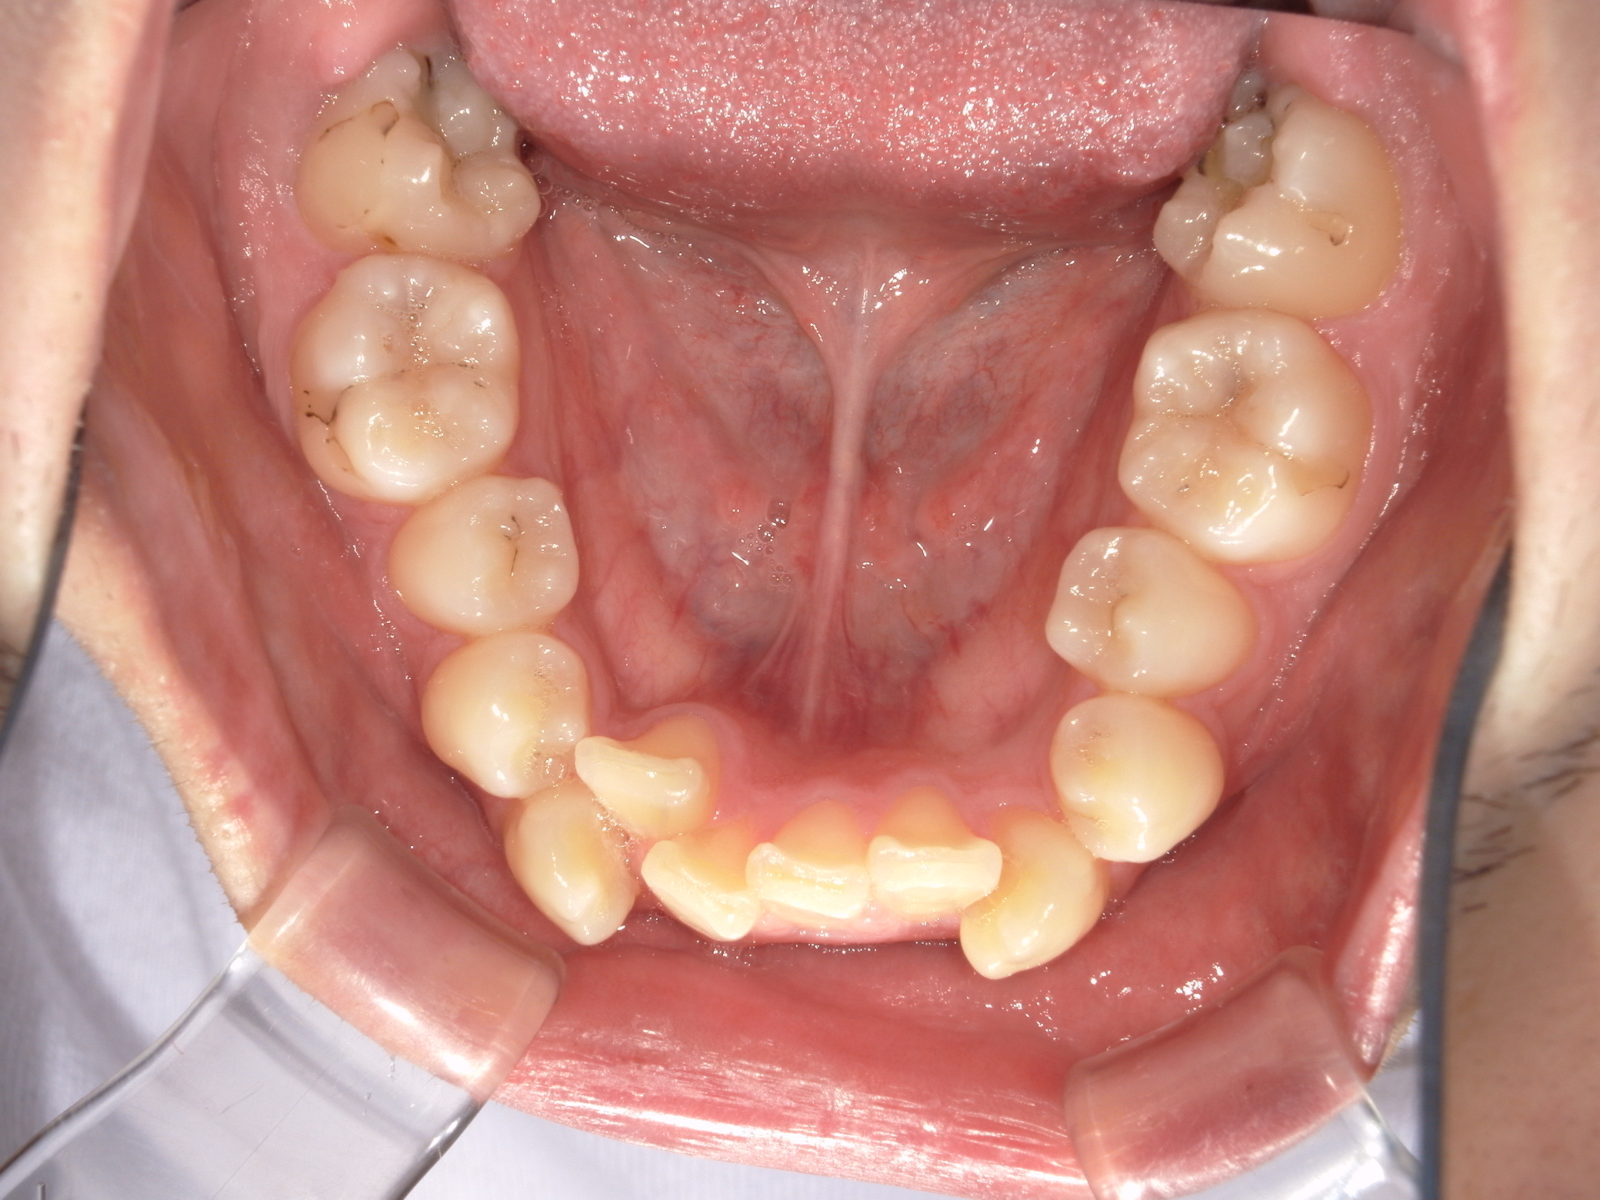

• 治療前

• 治療後

【主訴】歯のガタつき

【診断結果】叢生

【治療開始時の年齢】28歳

【治療内容】表側ワイヤー矯正+マウスピース型 (カスタムメイド) 矯正装置

【抜歯部位】上下左右4番目

【治療経過】後戻り無

【治療期間】1年11か月

【治療費用】1,001,000円

【リスク・副作用】

治療初期の段階では痛みや不快感が生じる可能性がある。適切に歯磨きをしないと虫歯になる可能性が高くなる。個人差により予想された治療期間より長くなる場合がある。治療後はリテーナーを装着しないと後戻りしてしまうリスクがある。